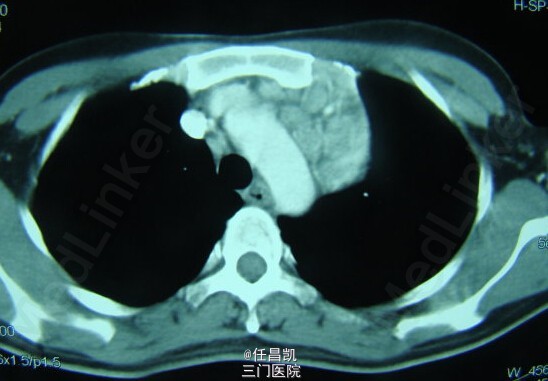

患者女,30岁,因胸闷不适4个月就诊,先后疑诊为肺癌、肺结核等治疗效果欠佳,进入我院。患者发病以来,无发热、咳嗽、血痰、胸痛等。

查体:心肺听诊无异,未见阳性体征。 辅查:CT如图所示。

入院诊断:肺部肿块待查 处理:入院后行手术探查+切除术治疗,术中快速病理检查排除恶性肿瘤,切除病灶,病理和免疫组织化学检查诊断为巨大淋巴结增生症。术后予补液、营养支持等对症处理,患者恢复顺利,复查CT无异,症状缓解遂出院。 出院诊断:胸内Castleman病